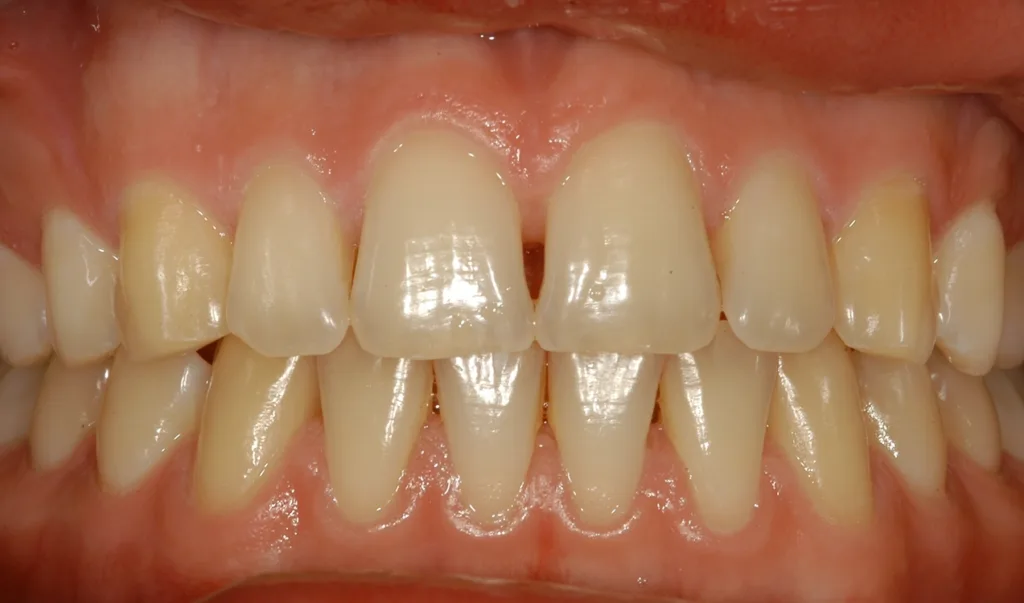

Die Ehlers-Danlos-Syndrome sind eine heterogene Gruppe von 13 unterschiedlichen Bindegewebserkrankungen, die alle durch Gelenkshypermobilitäten und überdehnbare und fragile Haut charakterisiert sind und je nach Typ mit unterschiedlichen weiteren Symptomen assoziiert sind [9]. Das parodontale Ehlers-Danlos-Syndrom (pEDS) ist das einzige der Ehlers-Danlos-Syndrome, das sich mit einer schweren Parodontitis im jugendlichen Alter, teilweise auch schon im Milchgebiss, manifestiert, da die Mutationen primär Gene der unspezifischen Immunantwort betreffen und erst in weiterer Folge die Bindegewebsschwäche verursachen [8] (Abb. 5, Abb. 6).

Die klinische Diagnose basiert auf der Trias der rasch progredienten Parodontitis im Teenageralter, dem kompletten Fehlen der befestigten Gingiva und der auffallenden Neigung zur Bildung von Hämatomen, die in zirka 80% der Betroffenen zu persistierenden Hämosiderin-Einlagerungen an den Schienbeinen führt. Die Parodontitis manifestiert sich teilweise schon im Milchgebiss, teilweise erst während der Pubertät und führt unbehandelt in wenigen Jahren zur Zahnlosigkeit. Das pEDS wird autosomal-dominant vererbt, sodass mindestens ein Elternteil ebenso an pEDS erkrankt ist; sehr selten kann es sich um eine Neumutation handeln. Die genetische Diagnose stützt sich auf die klinische Verdachtsdiagnose und wird durch den Nachweis pathogener Mutationen in den Komplement-1-Genen des C1S oder C1R gesichert.